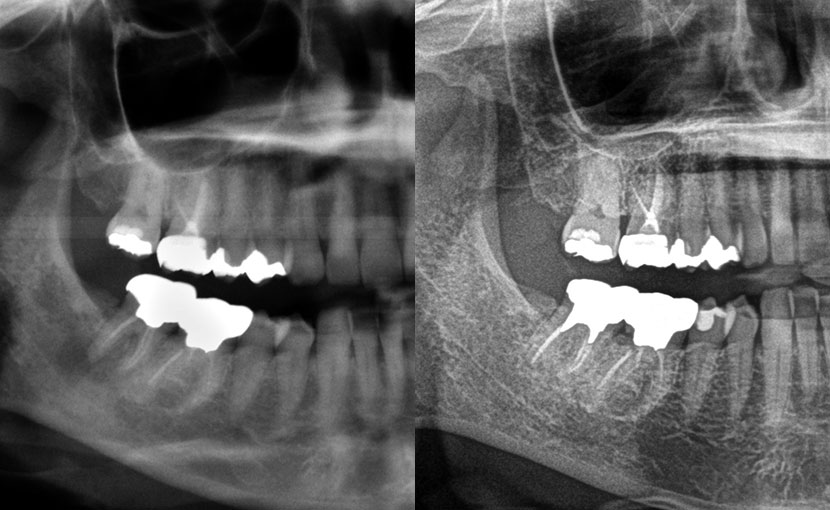

術前パノラマレントゲン写真

- パノラマ術前所見―向かって右下一番奥の歯(左下7番)の根っこの先が黒くなっている骨透過像を呈する。

パノラマレントゲン写真

11年後、当時の主訴であった左下一番奥(7番)の根っこの先の黒くなっている部分は白く改善されているように見えます。勿論、患者さんも以前の不都合は訴えていません。本当に改善しているかどうかは顎骨の内部(海綿骨の状態)を把握できる歯科用CTによる精査でしか正確に判断することはできません。そのため、歯科医院によって、診断の見解や術後の結果が全く違うと断言しておきましょう。

症状は訴えていなかった右上2番(向かって左上2番目)、左下6番(向かって右下奥から2番目)の根っこの先の化膿(透過像)も再根っこの治療で、改善しているように見えます。